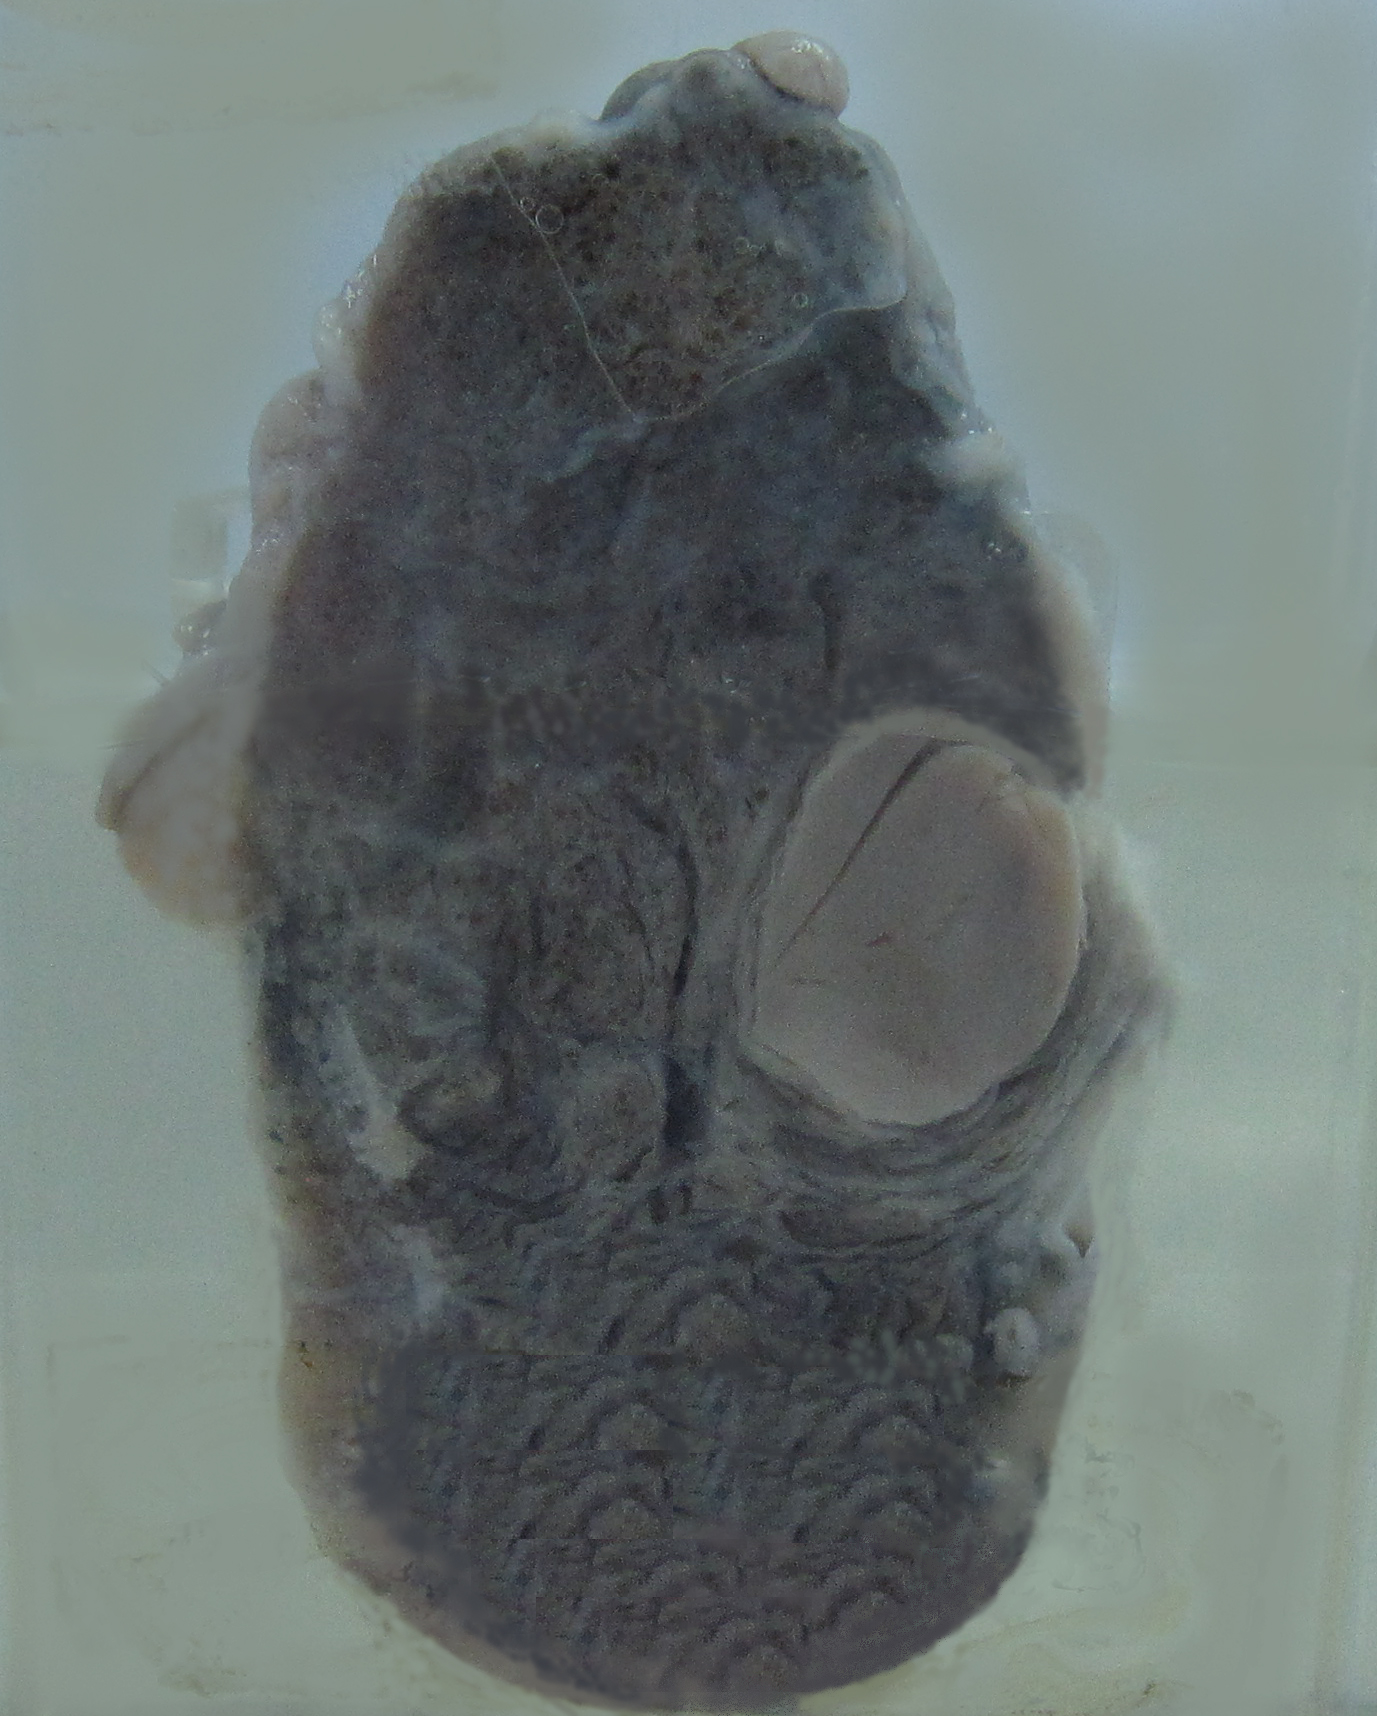

5. Adenoma of the thyroid